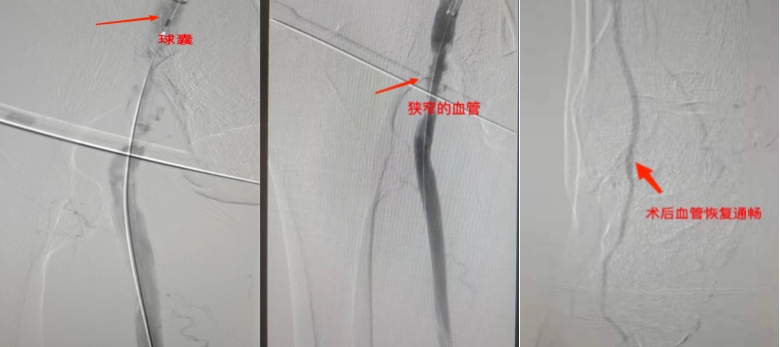

11月3日,在周围血管病科介入团队的精心操作下,患者进行了“右下肢动脉造影+右下肢股动脉+股浅静脉+腘动脉+胫前动脉球囊扩张成形术+吸栓术”。术中顺利清除血栓,恢复肢体血供。

对于慢性动脉血栓栓塞,一般是在动脉硬化闭塞的基础上逐渐形成的血栓栓塞,临床上现多采用介入治疗,一般采用球囊扩张、斑块旋切,以及支架植入等方式。微创介入治疗仅需局部麻醉,穿刺点直径仅为2mm,在DSA(数字减影血管造影)引导下,沿导丝将血栓抽吸导管送至血栓部位,然后抽吸清除血栓。整个手术时间短、创伤小,迅速恢复肢体血供,缓解疼痛症状,减少住院时间。